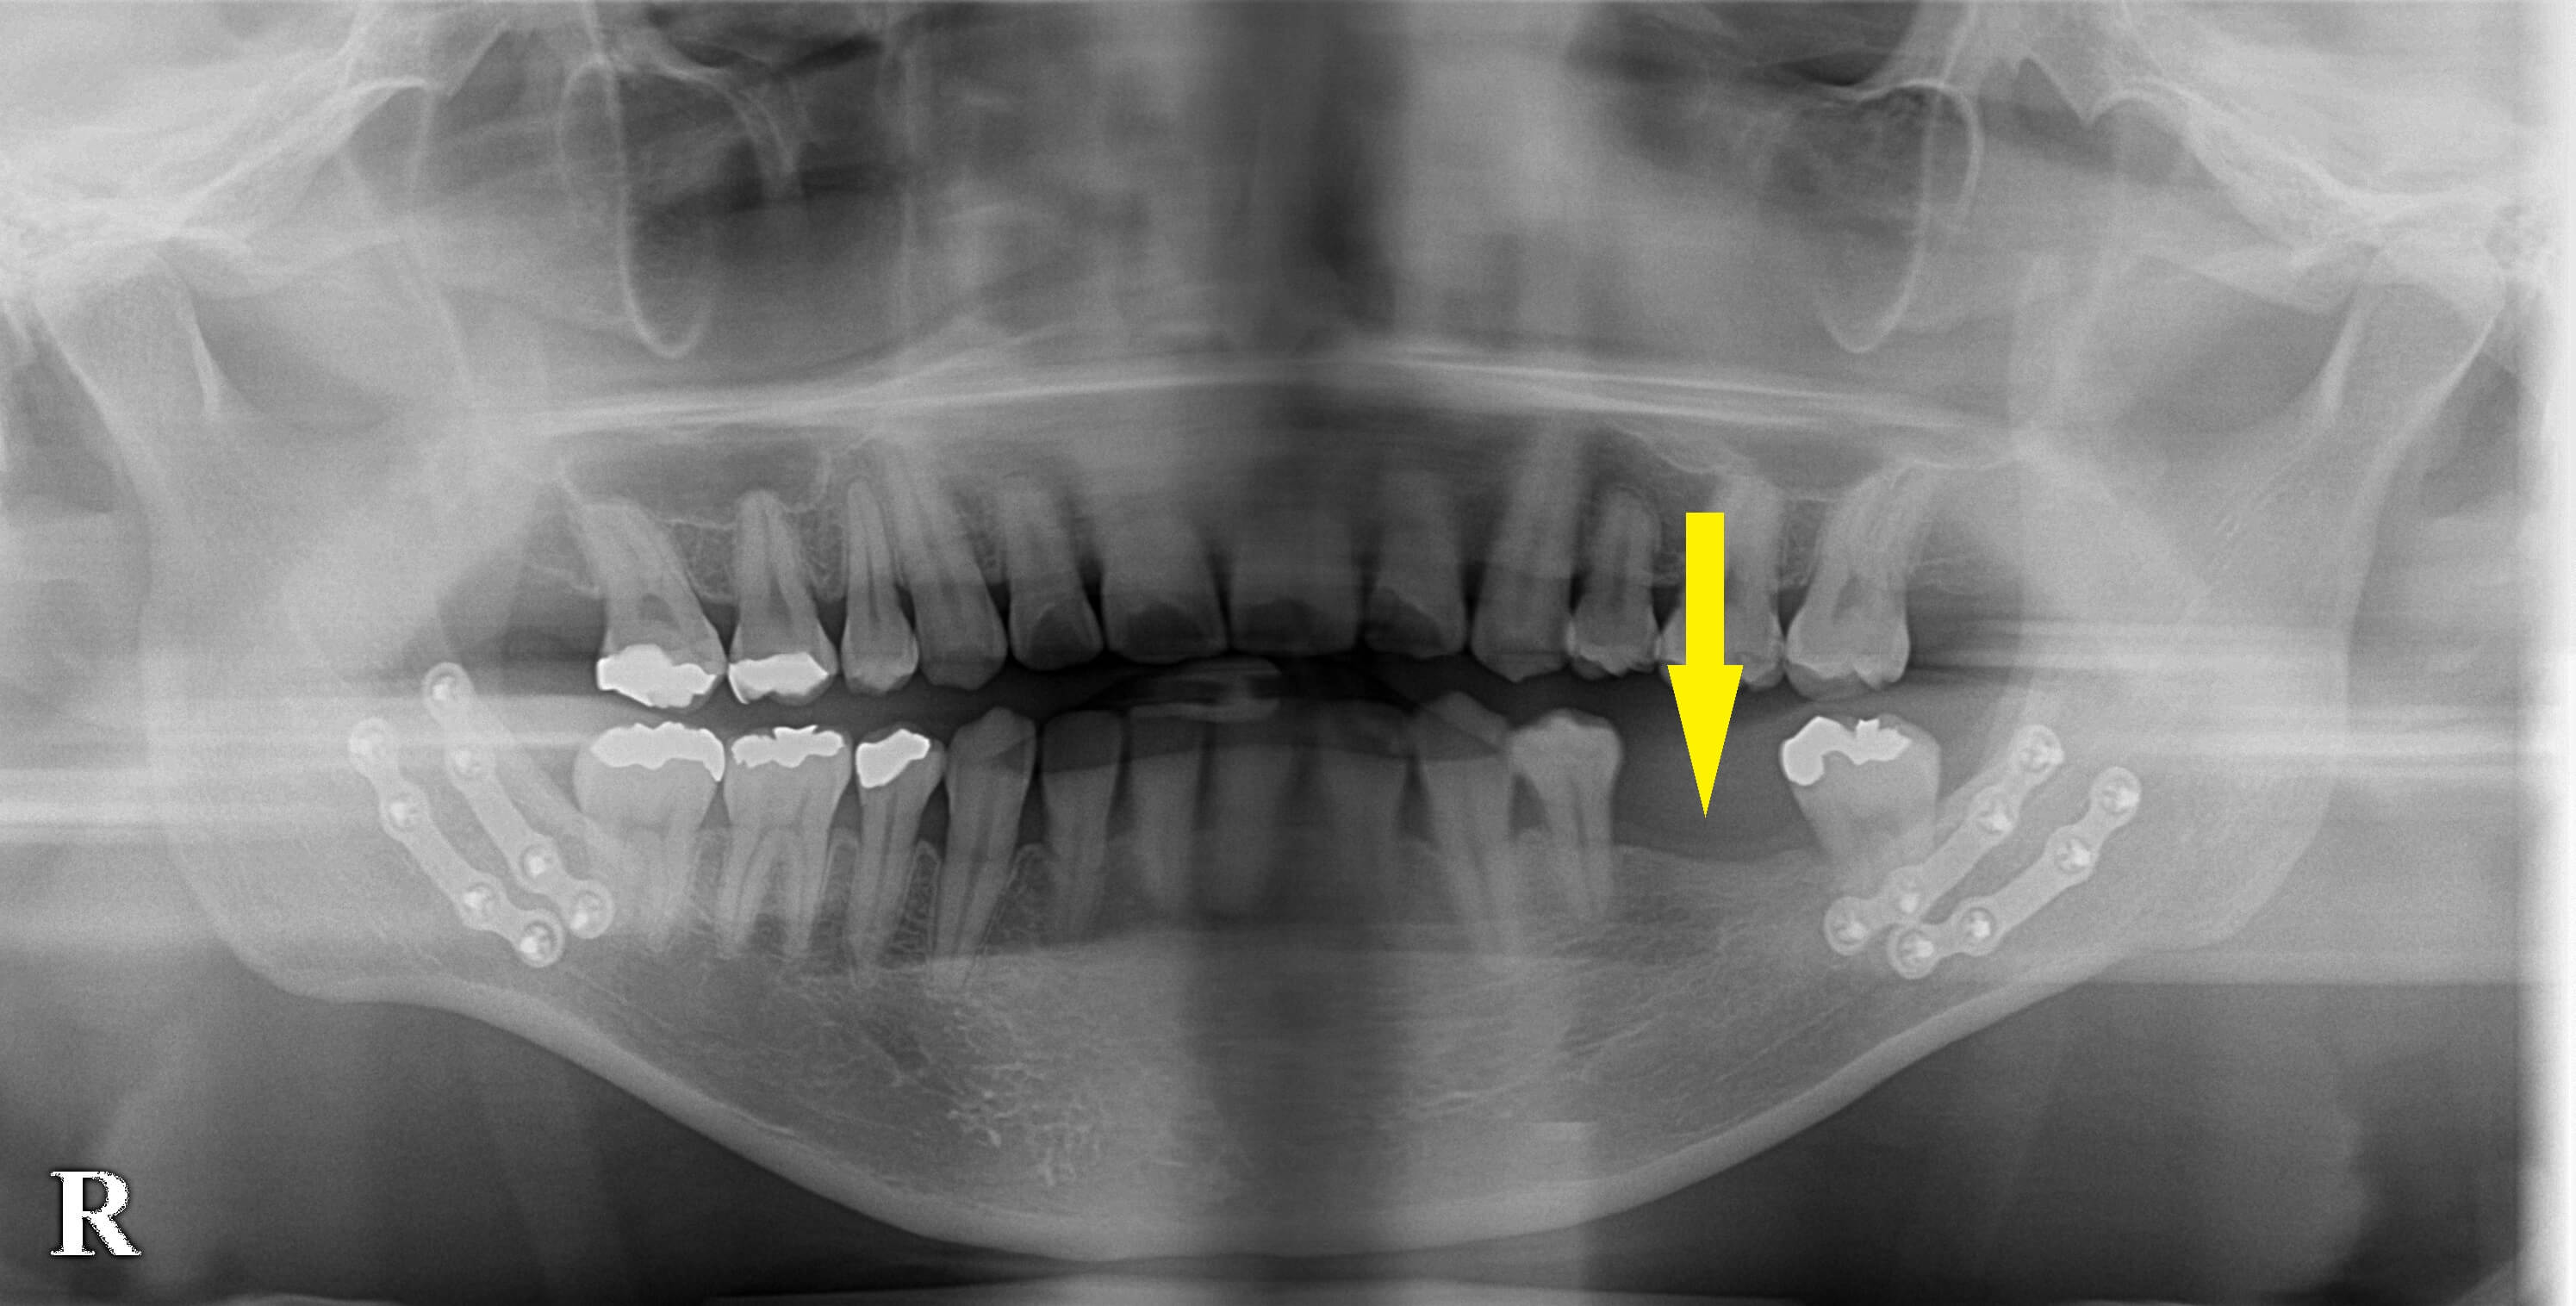

レントゲン写真で、骨切りの際に骨片を固定したチタンプレートが両側に残っているのが認められます。

本日1本のインプラント埋入術を行いました。